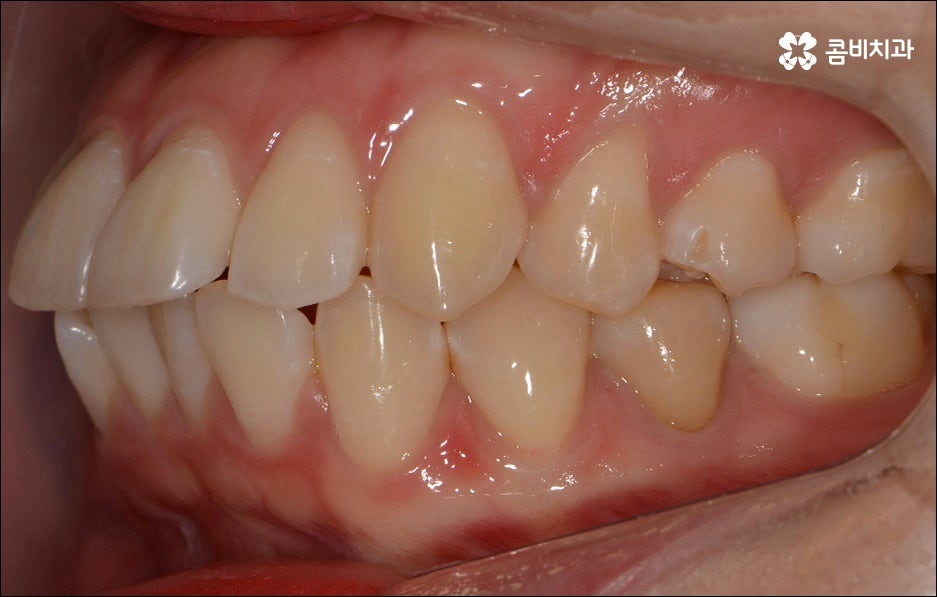

치열이 불규칙하여 기능적 심미적인 불편을 겪는 분들 중에 교정 치료를 고민하시는 분들이 많이 있습니다. 특히 앞니는 다른 치아보다 훨씬 외부에 잘 드러나므로 대화하거나 웃을 때 만약 앞니 사이가 벌어져 있거나 앞니 돌출 이 된 경우, 비틀어진 경우에는 신경이 많이 쓰일 수 있는데요. 하지만 막상 교정을 시작 하려고 하면 기간이 오래 걸리는 것 때문에 또는 치료 과정 자체에 부담을 느껴서 망설이시는 분들도 있을 수 있어요. 이때 앞니 외 다른 치아 배열 또는 위아래 교합에는 별다른 이상이 없다면 문제가 있는 앞니만 부분교정으로 치료할 수 있으니 이에 대해서 한 번 알아보시면 도움이 되실 거예요.

부분교정은 짧은 기간에 모든 치아가 아닌 특정 치아만 집중적으로 교정하는 것으로, 예를 들어 앞니 돌출 을 개선하기 위해 앞니와 그 옆의 치아까지 6~8개의 치아에만 브라켓을 장착하여 교정 치료를 하는 것을 의미하고 있어요. 비교적 간단한 과정이라고 생각하실 수 있으나 다른 치아에는 영향을 주지 않으면서 주변 치아와 앞니의 이동량을 고려하여 교합을 세밀하게 조정하고 전체 균형을 맞춰나가야 하는 만큼 의료진의 높은 숙련도가 필요한 과정이라고 할 수 있는데요.

만약에 앞니 돌출 이 각도만의 문제라면 이를 교정하기 위한 치료는 좀 더 간단하게 끝날 수 있습니다. 말씀드렸던 것처럼 상황에 따라 보다 빠른 부분교정을 통해 앞니만 교정 치료를 진행할 수도 있을 거예요.

하지만 보통은 돌출된 앞니 뿐 만 아니라 골격적인 부분이 원인이 되는 경우가 많으며 이런 경우에는 상태에 맞게 전체적으로 교정을 진행하여야 교합이 올바르게 되고 입매가 전체적으로 균형감 있게 개선될 수 있어요. 이런 경우에 골격적인 원인을 무시한 채 무리하게 치아의 각도만 안쪽으로 넣으려고 하면 자칫 옥니가 될 수도 있기 때문에 이러한 부작용을 막기 위해서도 환자분들의 상황을 정확하게 검진하고 그에 맞는 교정 플랜을 세우는 것이 필요한 거예요. 물론 부정교합 정도가 심각하고 골격적인 원인이 이미 굳어진 경우와 같이 수술이 함께 필요한 케이스도 있을 수 있으나 교정 치료만으로도 튀어나온 앞니가 들어가면서 자연스럽고 부드러운 인상으로 바뀌는 경우도 많으니 먼저 검진과 상담부터 꼼꼼하게 진행해 보시길 권유드리고 있습니다. 특히 개개인의 치열, 교합, 잇몸 상태, 구강구조 등을 면밀하게 파악하고 그에 따른 정확한 치료 계획을 수립할 수 있는 경험 많은 의료진과 함께 하는 것이 중요할 수 있어요.